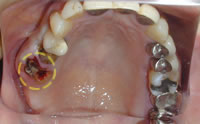

治療後

治療後治療後の状態